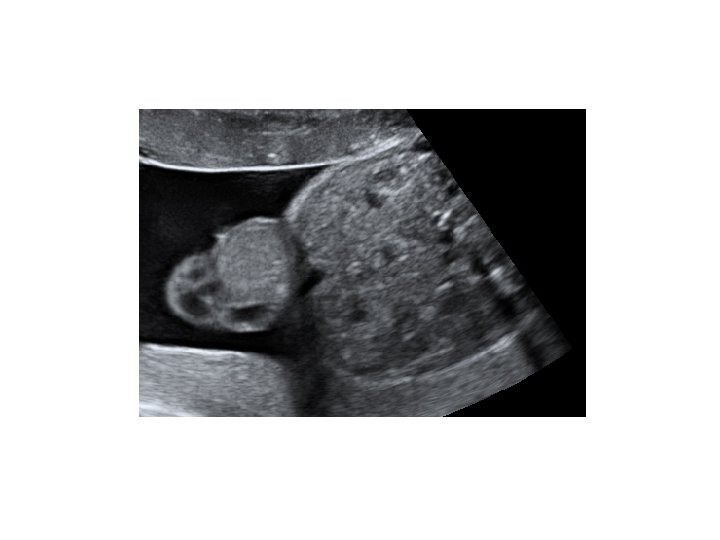

• Étude morphologique succincte : - pôle céphalique : structures cérébrales symétriques, voûte crânienne présente - membres : 4 x 3 segments - estomac : présent - vessie : présente - axe rachidien, insertion cordonale • Annexes : - trophoblaste - quantité de liquide • Ovaires

- thorax : cœur (position, 4 cavités équilibrées, septum inter ventriculaire, croisement Ao/AP), poumons - abdomen : paroi intègre, estomac (position, volume), vésicule biliaire, intestin grêle - arbre urinaire : vessie (position, volume), 2 reins - sexe - rachis avec son revêtement cutané - membres : 4 x 3 segments, 5 doigts aux 2 mains, mouvements d’ouverture des mains, mesure du pied